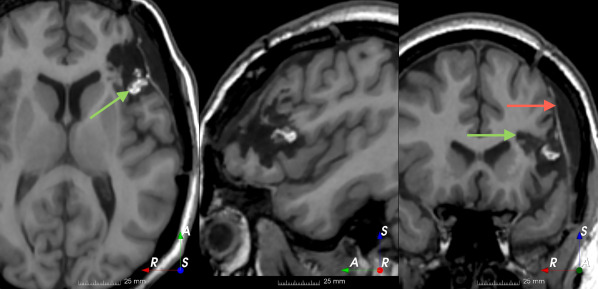

Refer to caption

(a)

(b)

(c)

(d)

(e)

(f)

Figure 3: Manual labels from Rater A (green) and Rater D, the model trained with PubFull + EpiPre + Pseudo (magenta). Errors caused by a (a) small resection, (b) blood clot in cavity and (c) brain shift; segmentations corresponding to the (d) 50th, (e) 75th and (f) 100th percentiles giving a DSC of 81.7, 86.5 and 93.8, respectively.